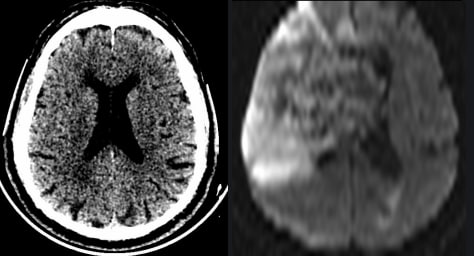

КТ на момент поступления и МРТ при ухудшении состояния через два дня.

Лаборант, по одной, ему лишь ведомой, причине, сделал МРТ фронтальными сканами, пришлось из фронтального сделать аксиальный, для лучшей сравнимости.

Интересно, что ИИ насчитал 9 баллов по ASPECTS, а глазом вообще ничего не видно было.

Тромболитическая терапия не проводилась из-за противопоказаний, через двое суток произошла спонтанная геморрагическая трансформация и инфаркт, как выяснилось, был не 9, а, скорее, 1 балл по ASPECTS.

Вот такие пироги...